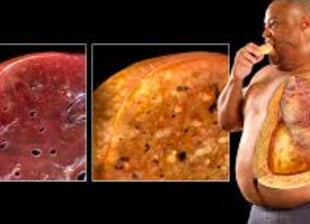

يمكن أن يحدث تلف خطير في الكبد، مما يؤدي إلى حالات مثل التشمع وحتى السرطان.

هناك نوعان رئيسيان من الكبد الدهني: مرض الكبد الدهني غير الكحولي (NAFLD) الذي يتضمن تراكم الدهون في الكبد، ومرض التهاب الكبد الدهني غير الكحولي (NASH) الذي يترافق مع علامات الالتهاب وتلف خلايا الكبد.

التهاب الكبد: يبدأ من حالة دهون إلى حالة ملتهبة (متورمة).

التليف: يتكون نسيج ندبي نتيجة الالتهاب الذي يؤدي إلى تلف الكبد.

تليف الكبد: حيث يتم استبدال الأنسجة السليمة بنسيج ندبي.

سرطان الكبد: يمكن أن يتطور نتيجة لهذه الحالات.